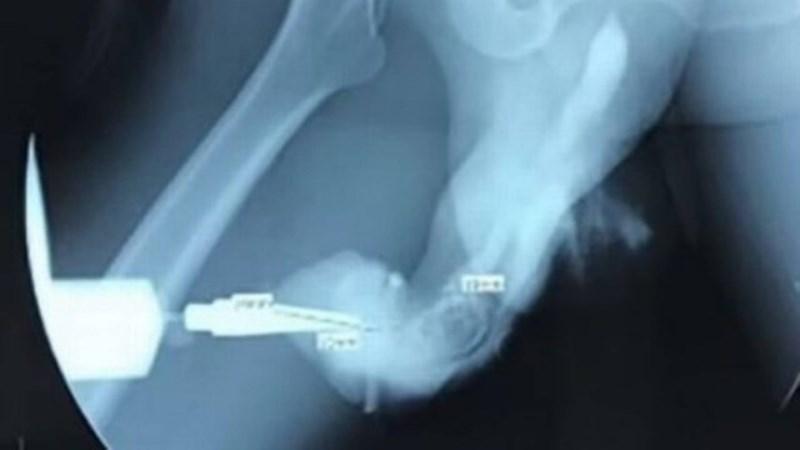

Homem de 50 anos sofre fratura no pênis durante ‘sexo mais vigoroso’Pênis fraturado após relação sexual 'mais vigorosa' na Indonésia – Foto: Reprodução/International Journal of Surgery Case Reports